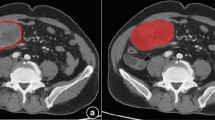

A total of 151 pathologically confirmed 1–2-cm gGISTs from seven institutions were identified by contrast-enhanced CT scans between January 2010 and March 2021. A detailed description of EUS morphological features was available for 73 gGISTs. The association between EUS or CT high-risk features and pathological malignant potential was evaluated. gGISTs were randomly divided into three groups to build the radiomics model, including 74 in the training cohort, 37 in validation cohort, and 40 in testing cohort. The ROIs covering the whole tumor volume were delineated on the CT images of the portal venous phase. The Pearson test and least absolute shrinkage and selection operator (LASSO) algorithm were used for feature selection, and the ROC curves were used to evaluate the model performance.

The presence of EUS- and CT-based morphological high-risk features, including calcification, necrosis, intratumoral heterogeneity, irregular border, or surface ulceration, did not differ between very-low and intermediate risk 1–2-cm gGISTs (p > 0.05). The radiomics model consisting of five radiomics features showed favorable performance in discrimination of malignant 1–2-cm gGISTs, with the AUC of the training, validation, and testing cohort as 0.866, 0.812, and 0.766, respectively.